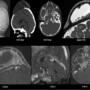

A 3-year-old male presented with nontender gradually progressive cystic swelling over the scalp for 9 months.

Radiograph of the skull showing large soft tissue swelling over the vertex with underlying bone erosion involving frontal and parietal bones with beveled edges.Non contrast CT brain shows a cystic scalp swelling with underlying bony erosion and erosion of petroclival synchondrosis.MRI-T2WI hyperintense large subperiosteal cystic lesion with peripheral soft tissue component with enhancement on post contrast T1WI.Enhancing and thickened pituitary stalk as well as enhancing soft tissue along right petrous apex and petroclival synchondrosis.

Final diagnosis –Langerhans Cell Histiocytosis